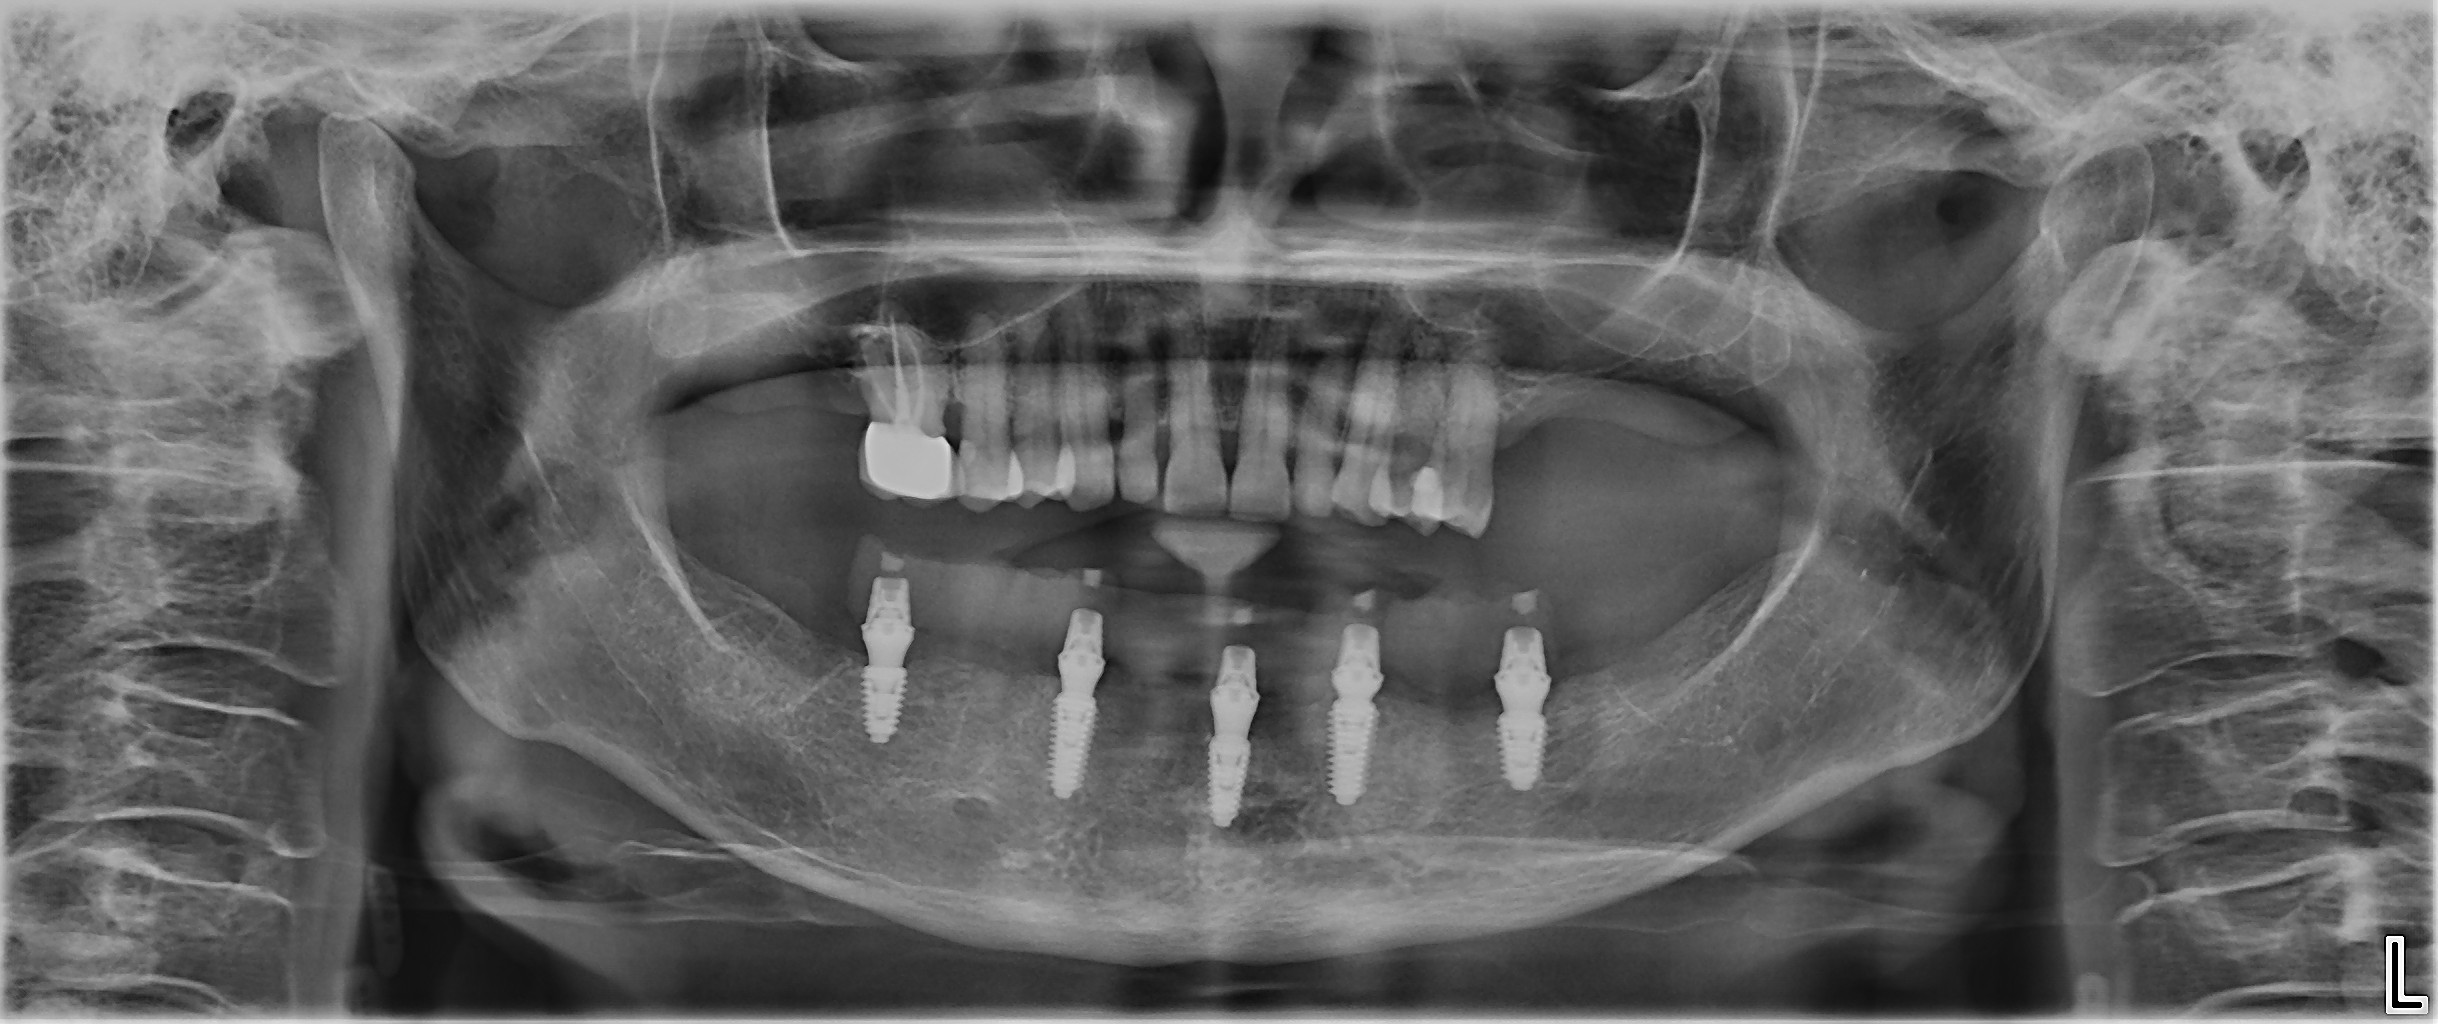

Fig. 1a: Pre-op panoramic radiograph. (All images: Dr Ádám Kapai, Dr Tamás Chikány, Tamás Csornai)

Intra-oral examination revealed compromised mandibular dentition, an old fixed prothesis, missing posterior teeth on the left side, periodontal involvement and gingival inflammation. A panoramic radiograph was obtained, and the findings were reported to the patient (Figs. 1a & b; 2a & b). Both mandibular canines had visible periapical radiolucencies. A CBCT scan was performed for a more detailed assessment of the alveolar bone anatomy (Figs. 3a & b). Temporomandibular joint examination revealed no indication of dysfunction (crepitus, clicking or pain).